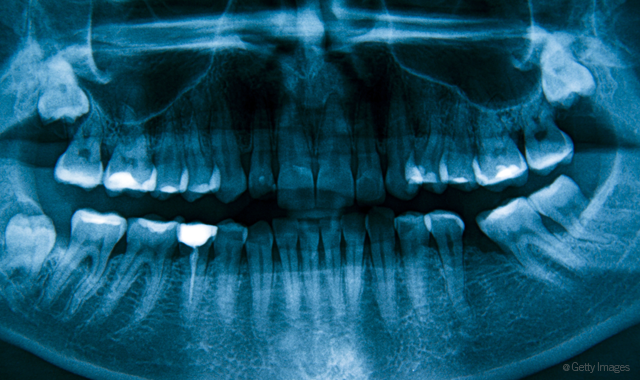

What do you tell a patient who asks how much radiation is given during routine X-rays?

First, I explain how there is much less radiation using digital radiographs than traditional. I like to state why radiographs are needed (we are working blind without them). Then, I like to give the patient examples of comparisons. For example, four bitewings equal 79 times less radiation than a year of background radiation from the environment. Four bitewings equal 0.5 mrem of radiation. In comparison:

Even eating a banana gives you more mrems than dental X-rays!